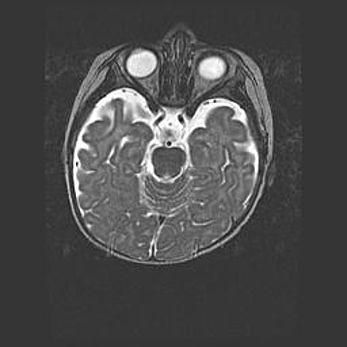

Аномалия Денди-Уокера. Признаки гипоплазии мозолистого тела.

Возраст: 5 месяцев 3 дня

Вес: 5550 г

Пол: мужской

Окружность головы: 39 см

Срок гестации: 40 недель

Аномалия Денди-Уокера – это порок развития головного мозга, для которого характерна триада симптомов: гипотрофия или аплазия червя мозжечка и/или полушарий мозжечка, расширение четвёртого желудочка с формированием ликворной кисты задней черепной ямки, гипертензионная гидроцефалия различной степени.

Гипоплазия мозолистого тела относится к дефектам внутриутробного этапа развития мозговой ткани, возникающим в процессе закладки структур головного мозга, что происходит на начальных этапах развития эмбриона.